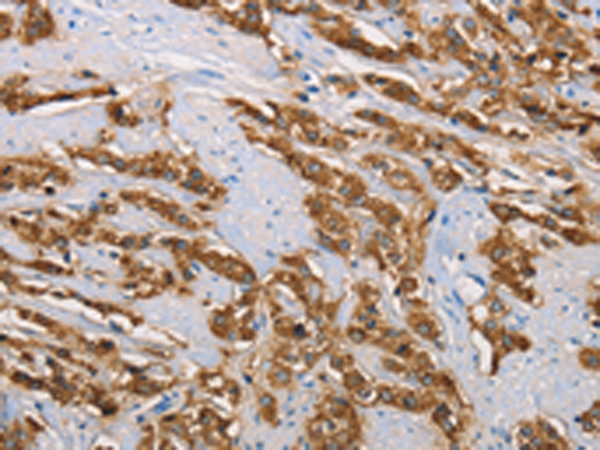

分类: 科研抗体货号: P07407别名: FLA10; KLP-20应用: WB,IHC反应种属: Human, Mouse